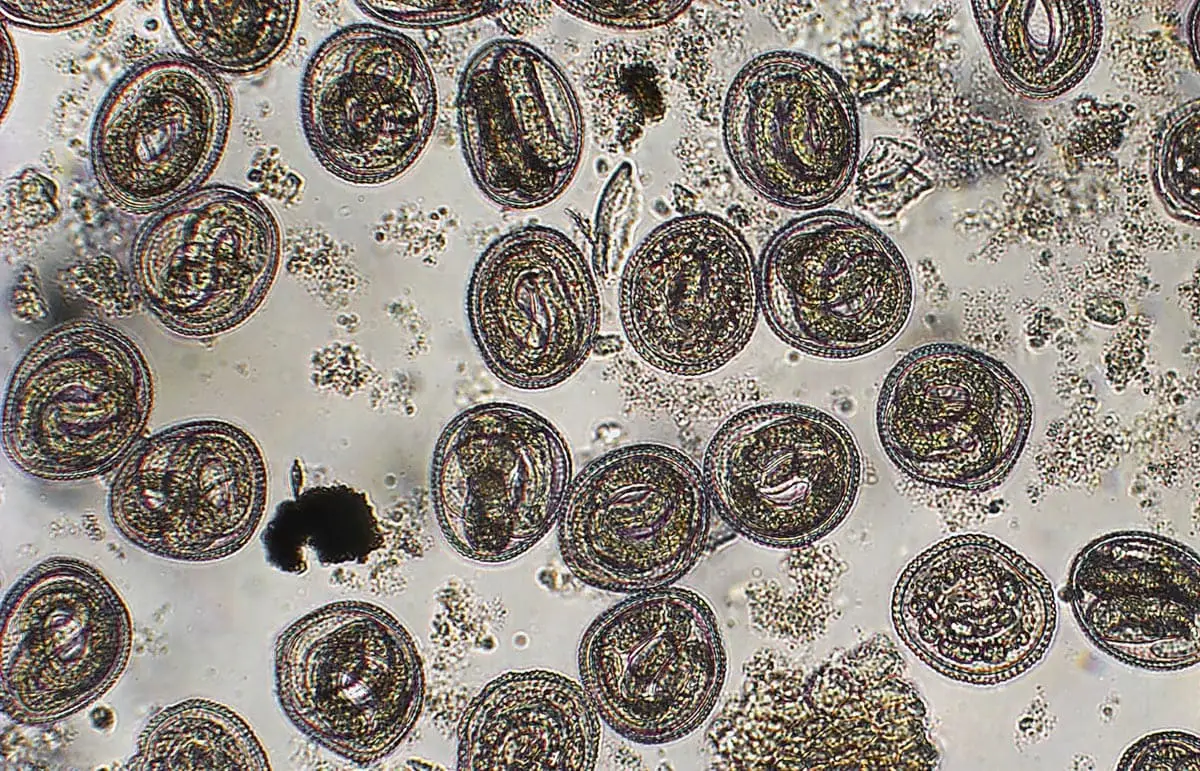

Skyld for infektion ( Sexnes Dette er de mest almindelige parasitter af katte. To typer skader for katte Katie Katie e Tokascaris Leon .

Infektion kan forekomme som et resultat af infektiøse æg i miljøet, da dette kan være af grundlæggende betydning i flere måneder eller år i væv eller modermælk.

dukke ansigt himalaya

De fleste voksne ture bor i fordøjelsessystemet hos gæster. Når katten spiser føtalæg, skal du fjerne tarmen, trænger ind i tarmvæggen og bevæger sig på leveren ind i lungerne. Derfra går de ind i vesiklerne og rejser gennem luftvejene. Larverne sluger og opnår tarmene, hvor de kommer ind i voksne og ser ud til at være befriet. En kolonne kan gøre det 200 000 ejer til tag Æg med lombig er ikke umiddelbart inficeret, men opnåelsen af larverne i det tredje trin (L3) tager 2-4 uger.

Hvis en voksen er forbundet med et skød af et spyd, kan nogle trænge ind i tarmvæggene, men opstår ikke i lungerne. Rejse i stedet til væv og organer og blive inaktive Ipiobiotico Larverne kan genoplive rutinehastigheder, der kommer ind i brystkirtlerne og flytter til mælkekatte.